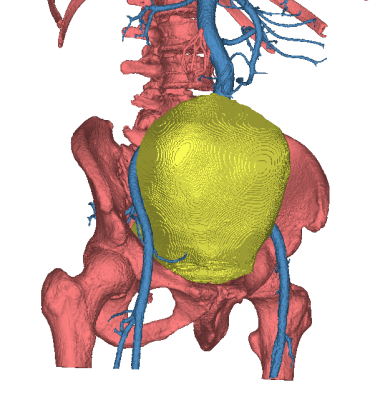

王先生住院后,医生们查阅他的各种影像资料后,均倒吸了一口凉气。王先生的肿瘤直径已达20多厘米,占据整个盆腔、周边紧压大血管和盆腔器官,手术切除犹如“虎口拔牙”,难度极大、风险极高,甚至可能引发大出血后死于手术台上。尽管王先生的家属早有心里准备,听完医生介绍病情后,看着饱受病痛折磨的父亲,家属与本人商量后,还是希望苏州大学附属第四医院的医生们能帮忙搏一搏。

术前影像学:占位范围广、周围比邻多支神经血管

在麻醉手术科和手术室护士团队的鼎力支持和密切配合下,手术如期进行。尽管已有一定的心理预期,但当打开腹腔的时候,巨大的肿物仍令在场的医护人员为之震惊。肿瘤范围大,界限不清、操作空间狭小,各种困难接踵而至。尤其肿瘤表面布满了“爬山虎”似的血管网,并与膀胱前列腺紧密粘在一起,每步操作都极易引发大出血。手术团队细心分离,历时4小时将约5斤重的盆腔巨瘤完整切除,并保住了王先生的膀胱、前列腺及肠道,避免了造瘘,提高了患者以后的生活质量。